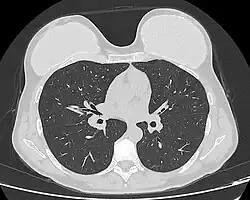

Silicone implant rupture can be evaluated using magnetic resonance imaging; from the long-term MRI data for single-lumen breast implants, the European literature about second generation silicone-gel breast implants (1970s design), reported silent device-rupture rates of 8–15 per cent at 10-years post-implantation (15–30% of the patients).[52][53][54][55] Additionally, high-resolution ultrasound is another effective method of evaluating silicone implant integrity.[56]

The study Safety and Effectiveness of Mentor's MemoryGel Implants at 6 Years (2009), which was a branch study of the U.S. FDA's core clinical trials for primary breast augmentation surgery patients, reported low device-rupture rates of 1.1 per cent at 6-years post-implantation.[57] The first series of MRI evaluations of the silicone breast implants with thick filler-gel reported a device-rupture rate of 1 percent, or less, at the median 6-year device-age.[58] Statistically, the manual examination (palpation) of the woman is inadequate for accurately evaluating if a breast implant has ruptured. The study, The Diagnosis of Silicone Breast implant Rupture: Clinical Findings Compared with Findings at Magnetic Resonance Imaging (2005), reported that, in asymptomatic patients, only 30 per cent of the ruptured breast implants are accurately palpated and detected by an experienced plastic surgeon, whereas MRI examinations accurately detected 86 per cent of breast implant ruptures.[59] Therefore, the U.S. FDA recommended scheduled MRI examinations, as silent-rupture screenings, beginning at the 3-year-mark post-implantation, and then every two years, thereafter.[25] Nonetheless, beyond the U.S., the medical establishments of other nations have not endorsed routine MRI screening, and, in its stead, proposed that such a radiologic examination be reserved for two purposes: (i) for the woman with a suspected breast implant rupture; and (ii) for the confirmation of mammographic and ultrasonic studies that indicate the presence of a ruptured breast implant.[60]

Furthermore, The Effect of Study design Biases on the Diagnostic Accuracy of Magnetic Resonance Imaging for Detecting Silicone Breast Implant Ruptures: a Meta-analysis (2011) reported that the breast-screening MRIs of asymptomatic women might overestimate the incidence of breast implant rupture.[61] In the event, the U.S. Food and Drug Administration emphasised that "breast implants are not lifetime devices. The longer a woman has silicone gel-filled breast implants, the more likely she is to experience complications."[62]